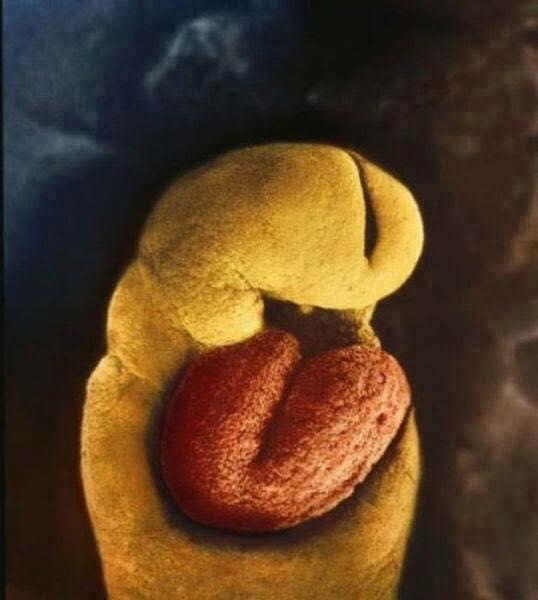

24 dias, o embrião não tem esqueleto mas já tem um coração

4 semanas, seus olhos começam a se formar e começa o desenvolvimento do que será mais tarde os braços e pernas

40 dias, já é possível ver as células da placenta, encarregadas de conectar o embrião com a parede uterina permitindo a chegada dos nutrientes através da corrente sanguínea da mãe.